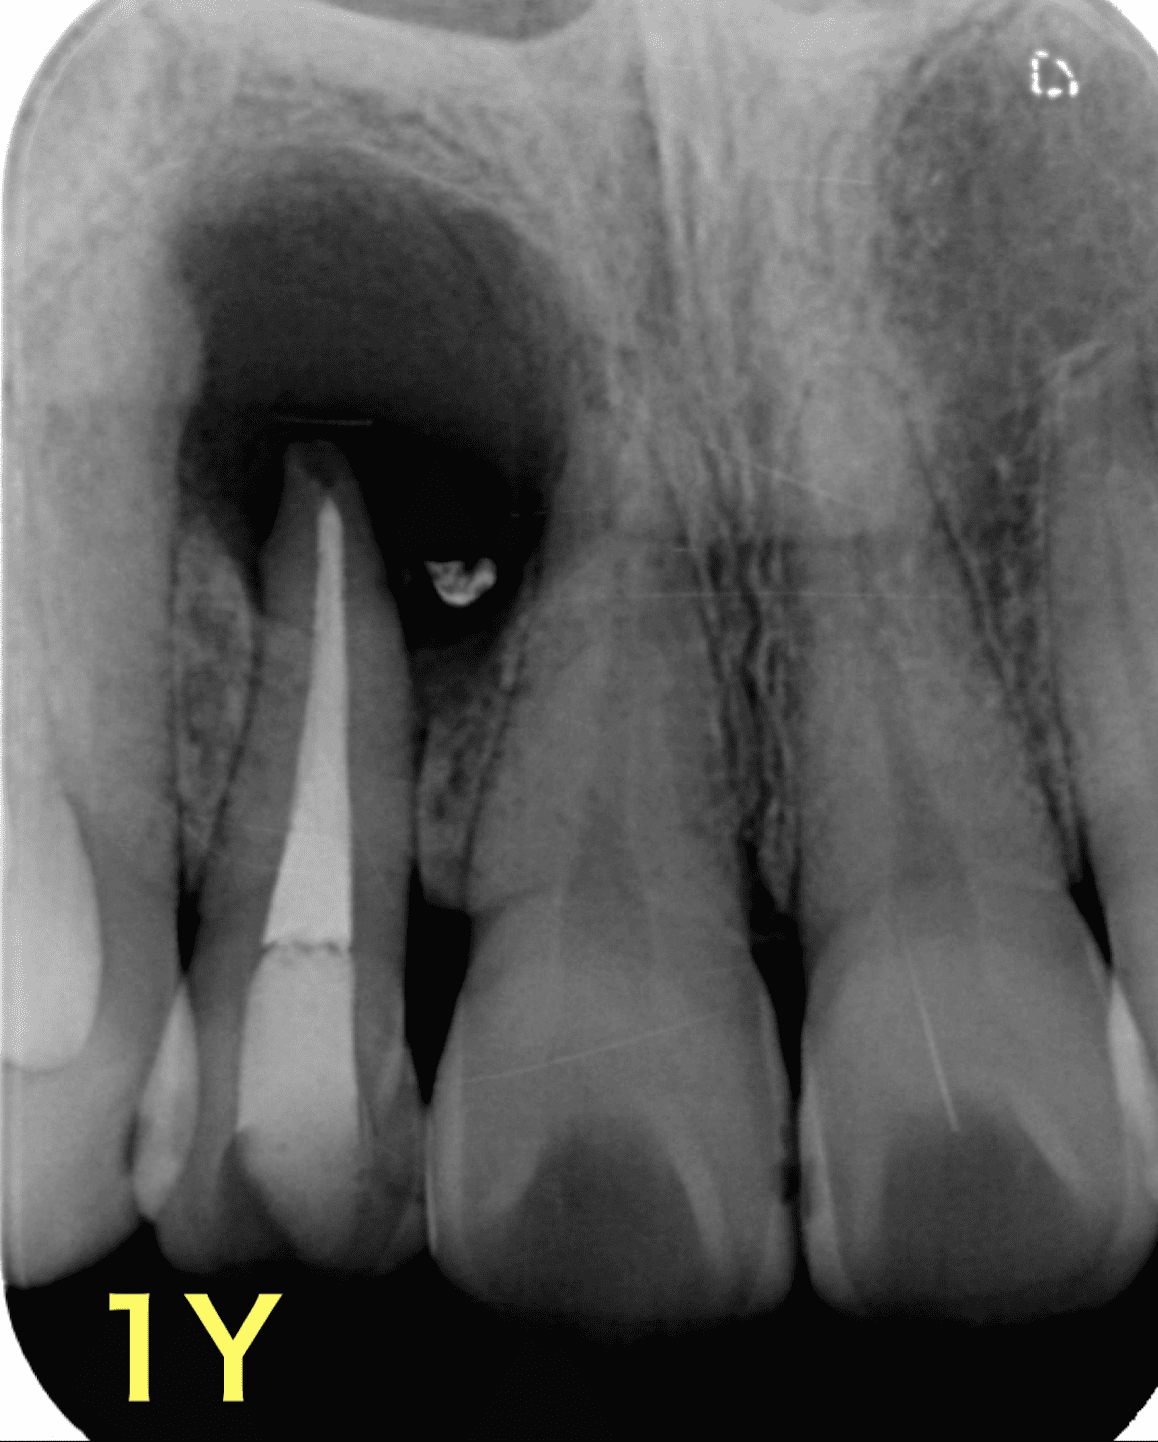

再根管治療8年後の経過

治療前

再根管治療後1年で病変の大きさに変化なく、ここで外科治療に踏み切りたくなりますが。。